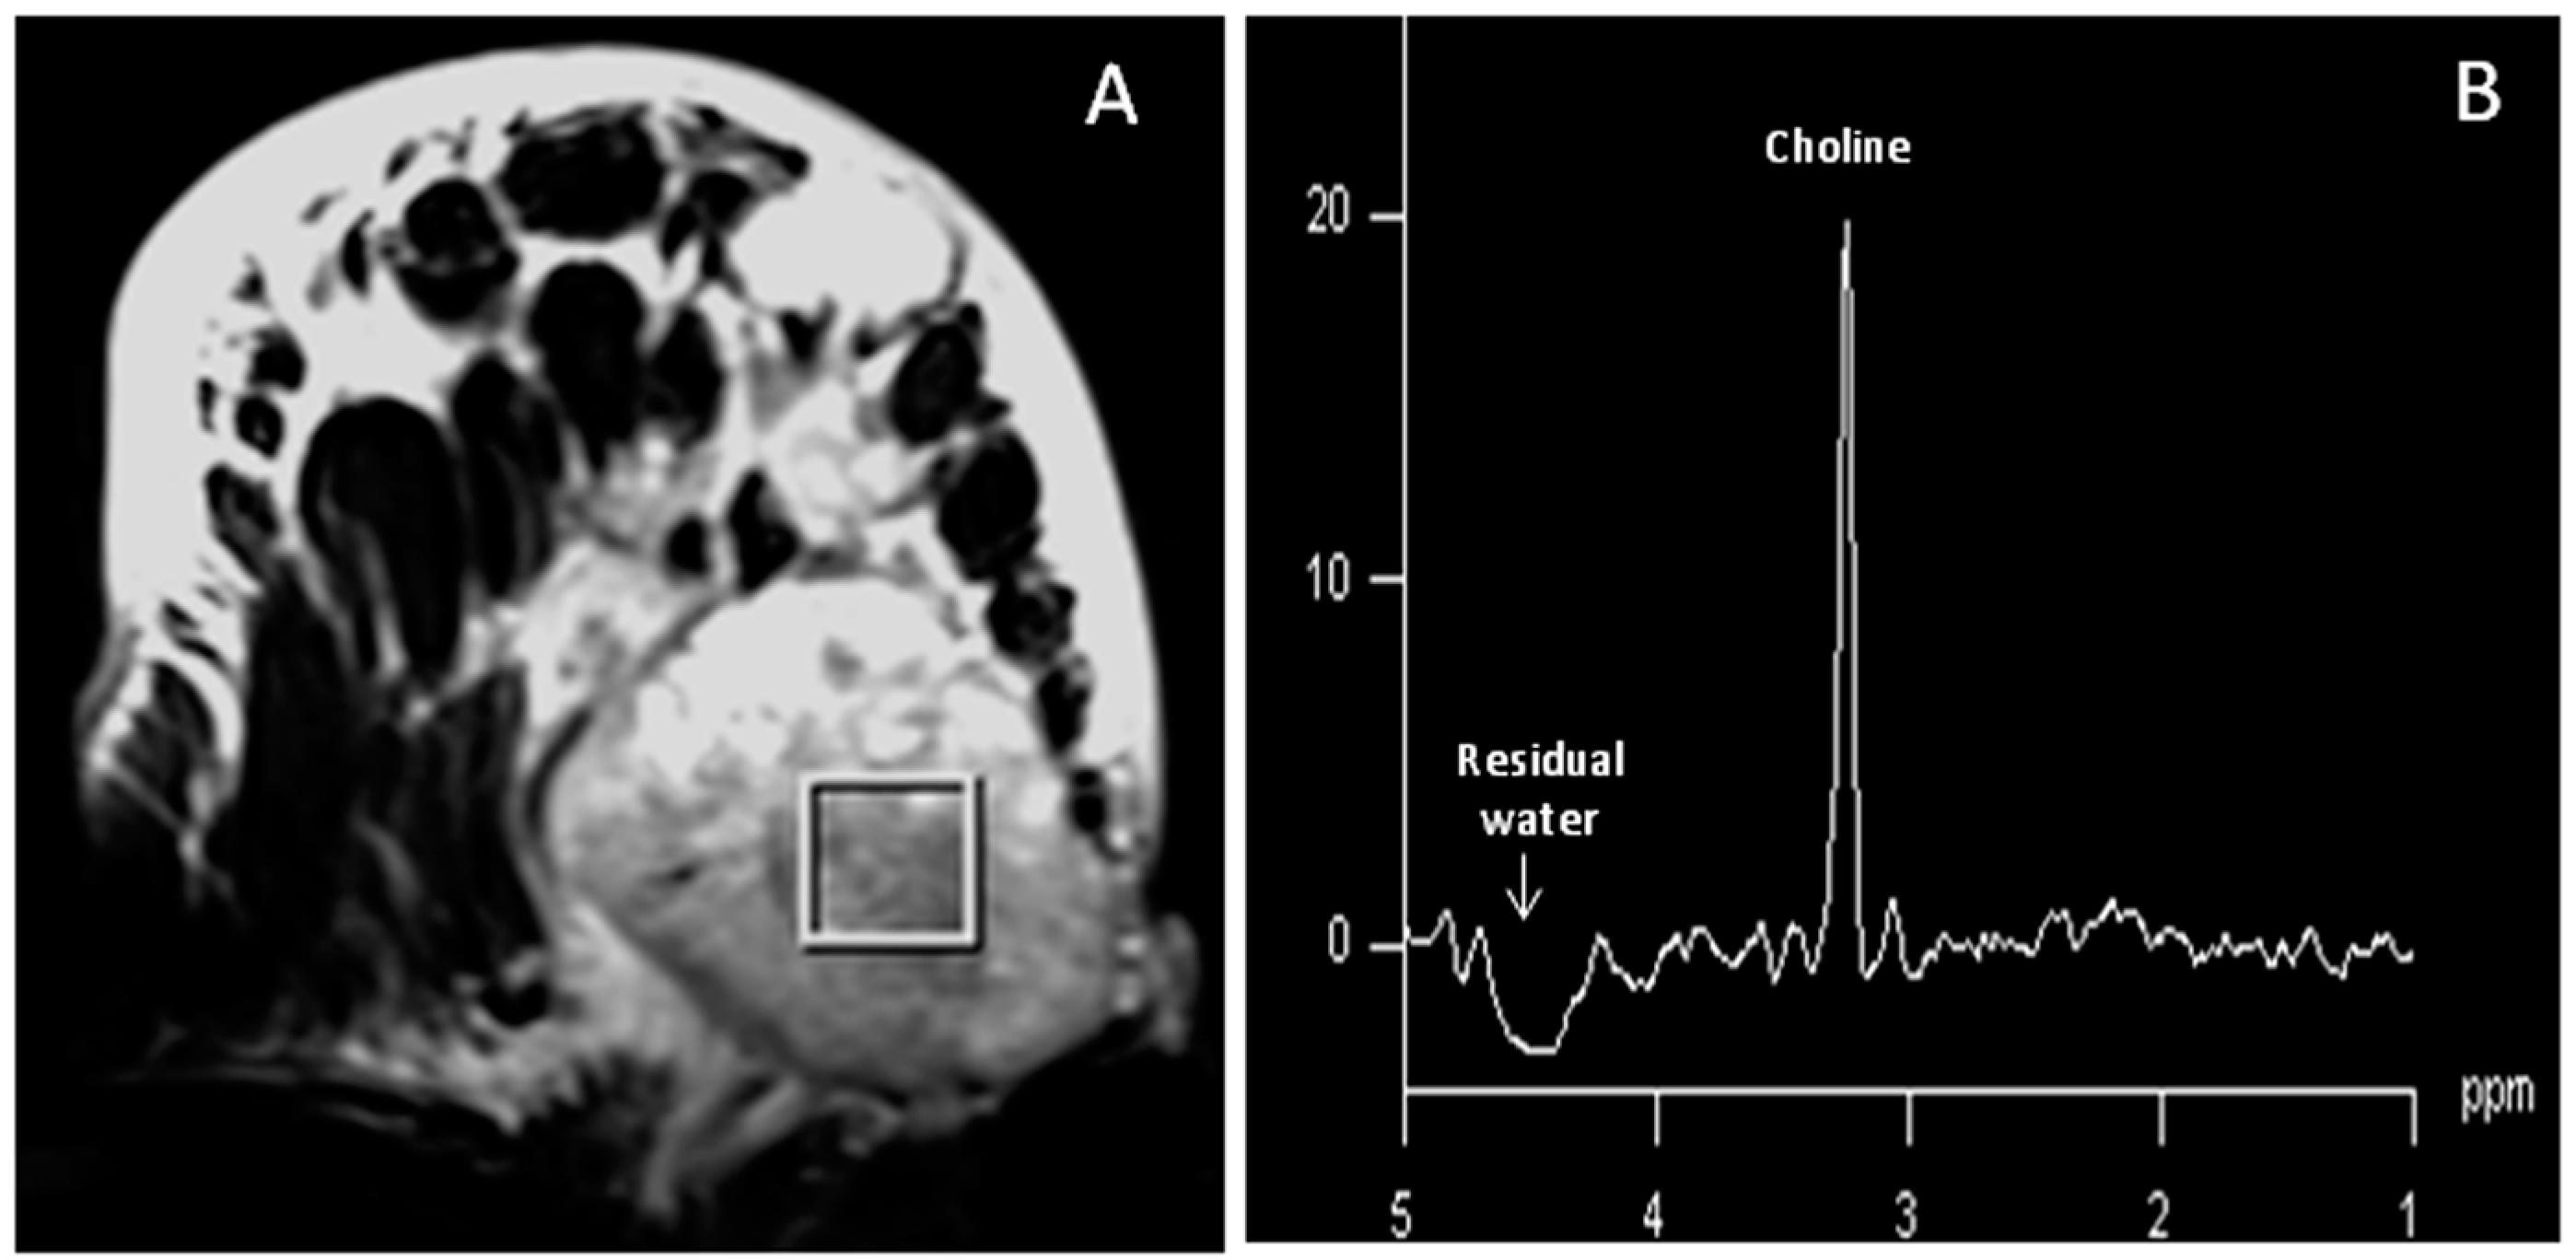

- Jagannathan, N.R.; Kumar, M.; Seenu, V.; Coshic, O.; Dwivedi, S.N.; Julka, P.K.; Srivastava, A.; Rath, G.K. Evaluation of total choline from in vivo volume localized proton MR spectroscopy and its response to neoadjuvant chemotherapy in locally advanced breast cancer. Br. J. Cancer 2001, 84, 1016–1022. [Google Scholar] [CrossRef] [PubMed]

- Sah, R.G.; Sharma, U.; Parshad, R.; Seenu, V.; Mathur, S.R.; Jagannathan, N.R. Association of estrogen receptor, progesterone receptor, and human epidermal growth factor receptor 2 status with total choline concentration and tumor volume in breast cancer patients: An MRI and in vivo proton MRS study. Magn. Reson. Med. 2012, 68, 1039–1047. [Google Scholar] [CrossRef] [PubMed]

- Sah, R.G.; Agarwal, K.; Sharma, U.; Parshad, R.; Seenu, V.; Jagannathan, N.R. Characterization of malignant breast tissue of breast cancer patients and the normal breast tissue of healthy lactating women volunteers using diffusion MRI and in vivo 1H MR spectroscopy. J. Magn. Reson. Imaging 2015, 41, 169–174. [Google Scholar] [CrossRef] [PubMed]

- Thakur, S.B.; Brennan, S.B.; Ishill, N.M.; Morris, E.A.; Liberman, L.; Dershaw, D.D.; Bartella, L.; Koutcher, J.A.; Huang, W. Diagnostic usefulness of water-to-fat ratio and choline concentration in malignant and benign breast lesions and normal breast parenchyma: An in vivo 1H MRS study. J. Magn. Reson. Imaging 2011, 33, 855–863. [Google Scholar] [CrossRef] [PubMed]